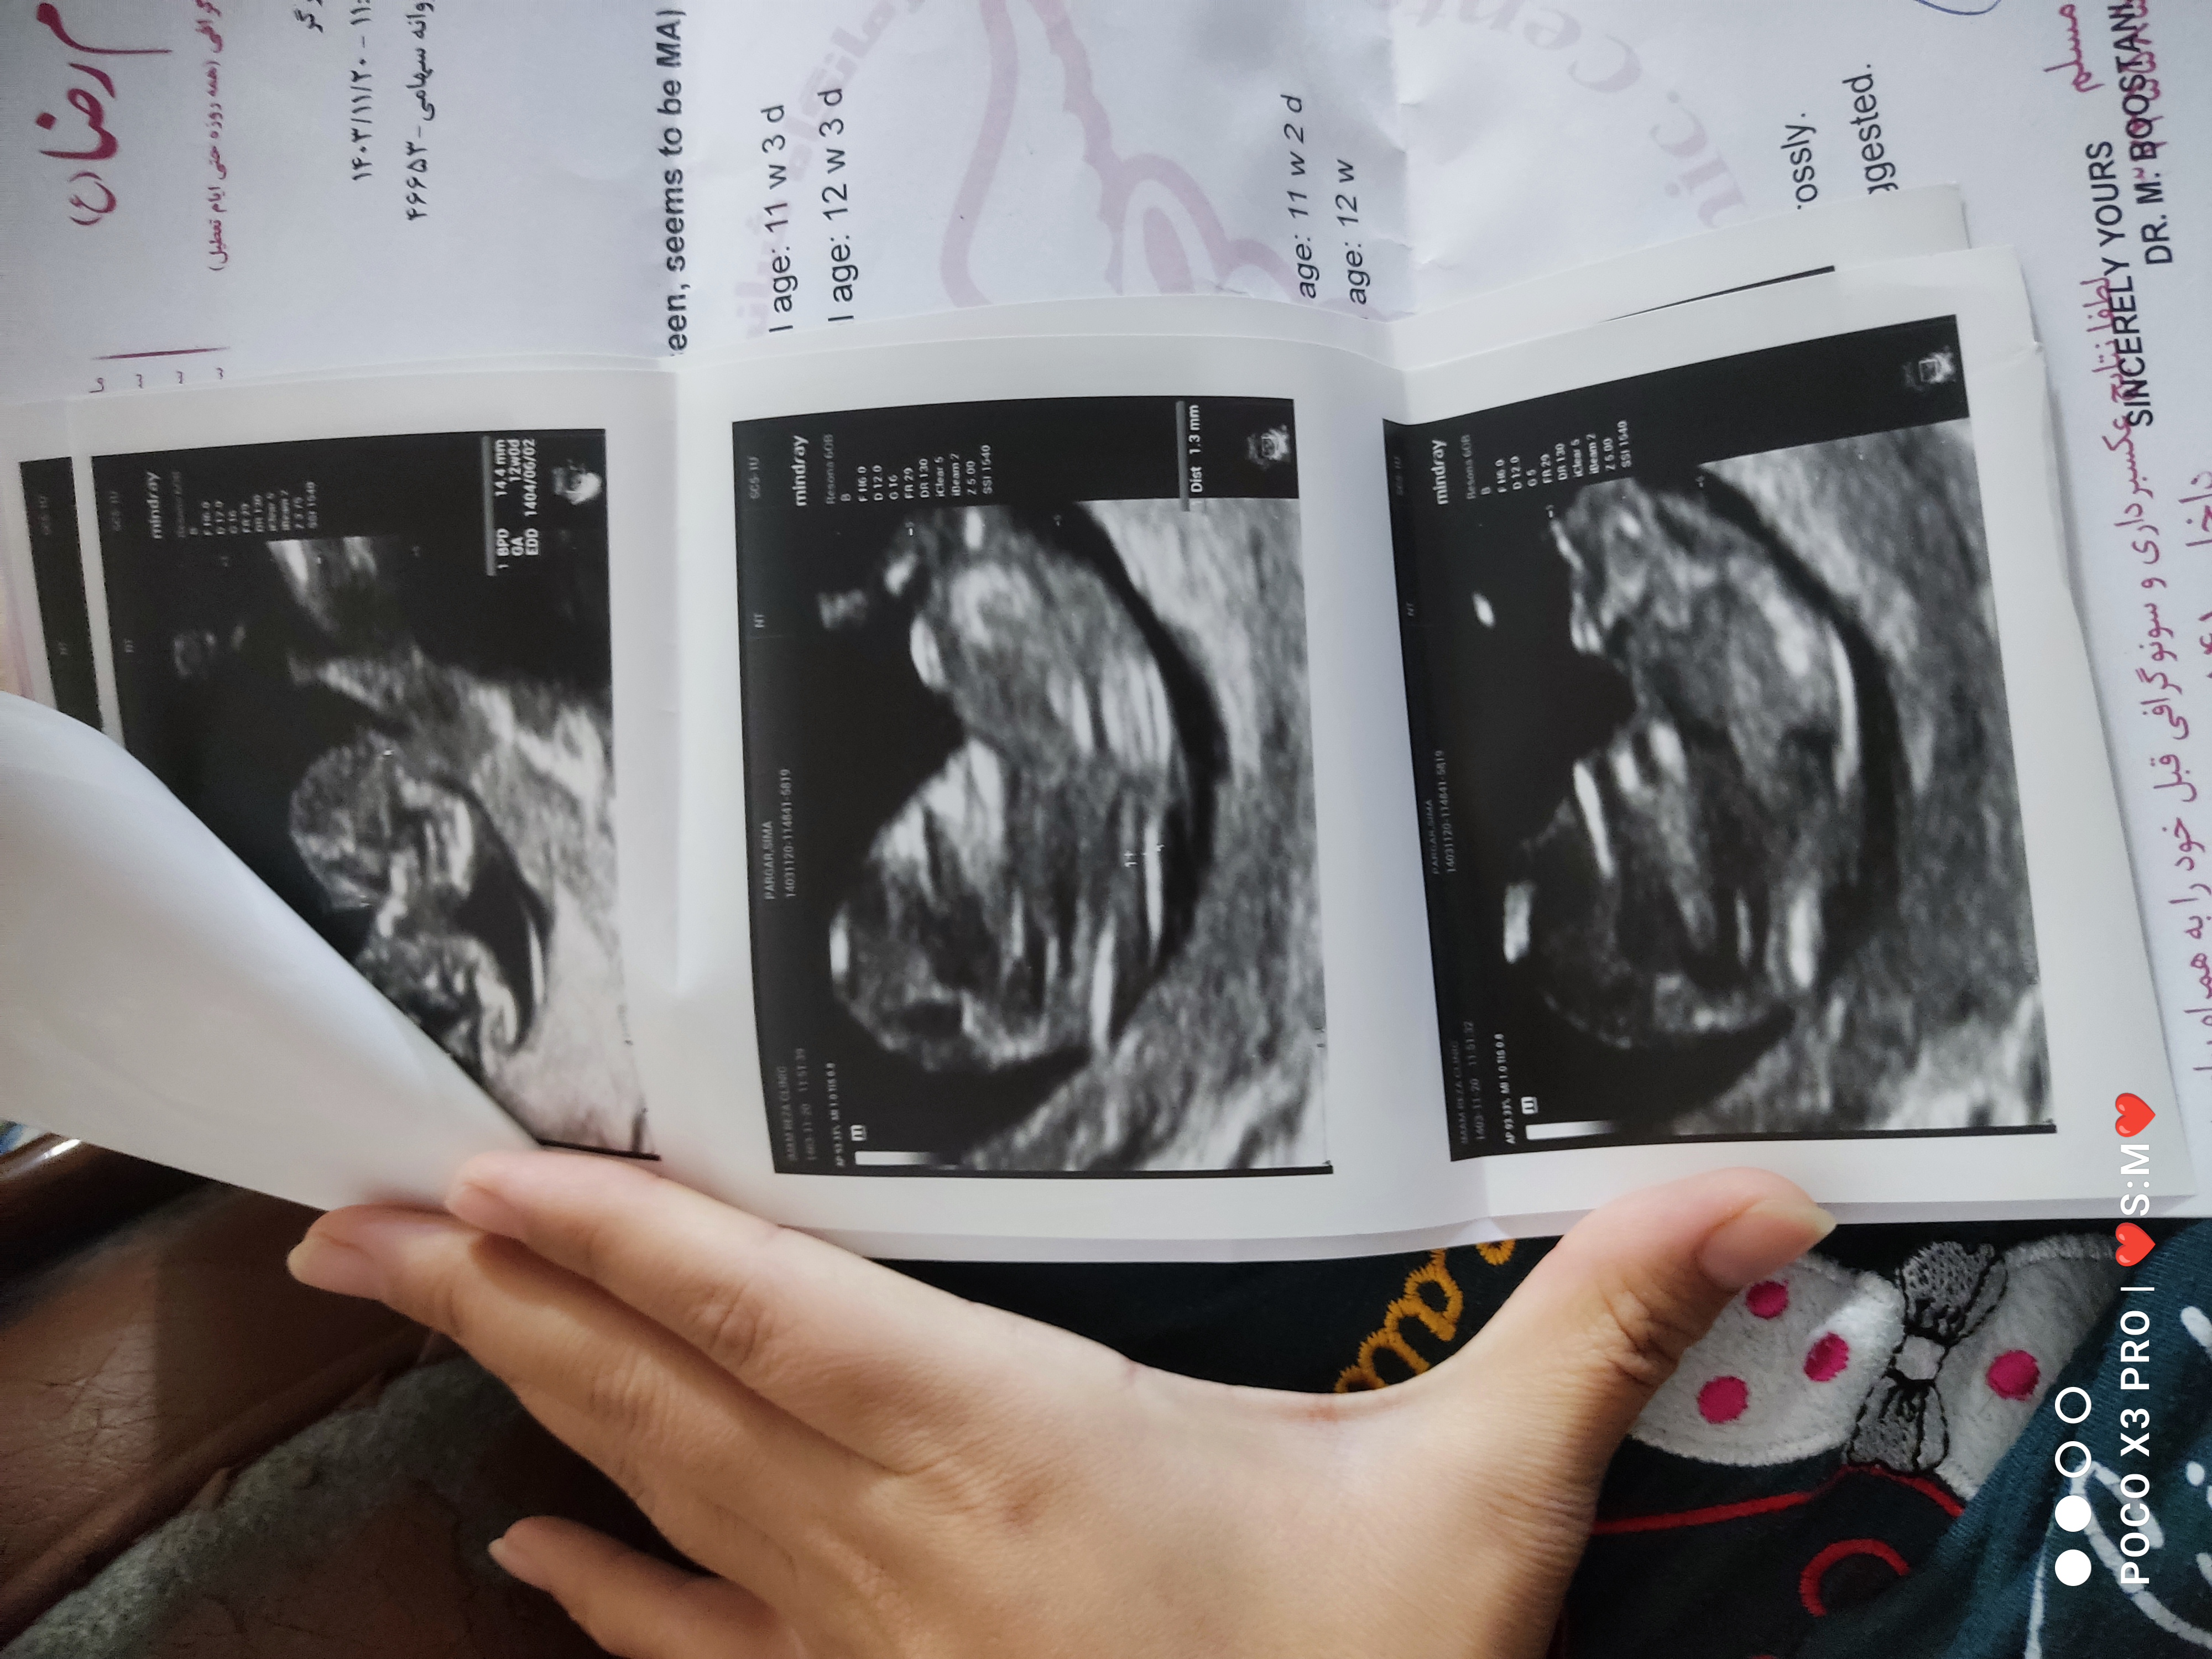

توت_فرنگی0 مدیر استارتر عضویت: 1403/05/20 تعداد پست: 41 عنوان جنسیت نی نی 86 بازدید | 10 پست سلام ..عکس میزارم میتونید حدس بزنید جنسیتشون رو؟؟؟ 1403/12/04 | 00:27 0 نفر لایک کرده اند ... گزارش تاپیک نامناسب

توت_فرنگی0 مدیر استارتر عضویت: 1403/05/20 تعداد پست: 41 حس ششمم گف دختره ایشالا سالم باشه هر چی هس مرسی عزیزم